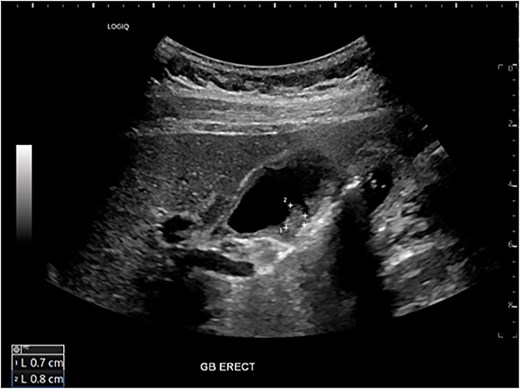

A 54-year-old female with a recent diagnosis of IBD complicated by PSC, presenting with right upper quadrant pain, underwent abdominal ultrasound, and magnetic resonance cholangiopancreatography (MRCP) as part of her PSC workup. Ultrasound demonstrated two 7 mm gallbladder polyps, with a normal gallbladder wall. MRCP demonstrated segmental intrahepatic duct dilatation in segments II and VIII in keeping with PSC (Fig. 1). Initial liver function tests and Ca 19.9 level showed only a mildly elevated GGT and ALP. Due to the recent diagnosis of IBD and small size of gallbladder polyps, observation with progress imaging at 12 months was undertaken. Repeat MRCP demonstrated a slight outpouching of the wall of the gallbladder with subtle enhancement of the lateral wall, with no concerning features for malignancy.

Magnetic resonance imaging liver/MRCP demonstrating subtle intrahepatic biliary dilatation (arrows), most pronounced in segment 8.

Six months after surveillance imaging, she was presented with ongoing abdominal pain. Liver function tests (LFTs) and Ca 19–9 remained normal at this time. A repeat abdominal US demonstrated an irregular gallbladder wall with thickening up to 5 mm and two stable gallbladder polyps, the largest measuring 7 × 8 mm (Fig. 2). Due to ongoing symptoms and changes on imaging, a laparoscopic cholecystectomy with intraoperative cholangiogram was performed without complication. At the time of surgery, the gallbladder was noted to have an area of wall thickening thought to be a Phrygian cap. The operative cholangiogram was consistent with PSC, with narrowed intrahepatic ducts observed (Fig. 3).

Preoperative ultrasound showing gallbladder polyp and wall thickening.